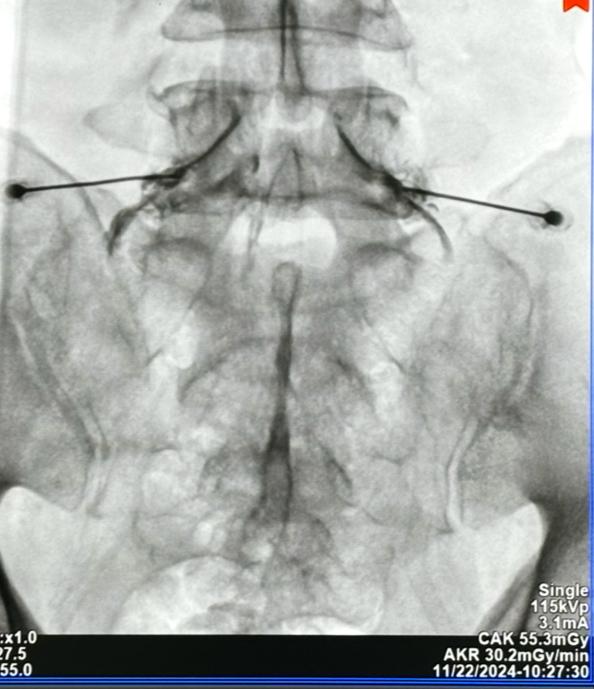

Bloqueo transforaminal de L5 bilateral por dolor radicular tipo corriente severo irradiado a ambos miembros inferiores